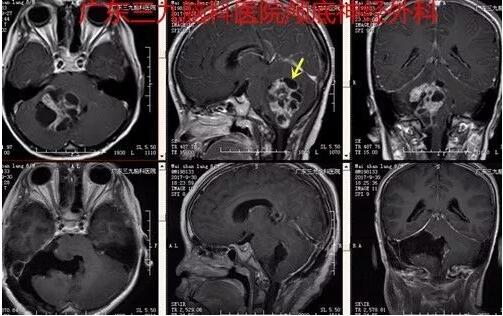

图4:术前术后MR对比提示肿瘤全切除